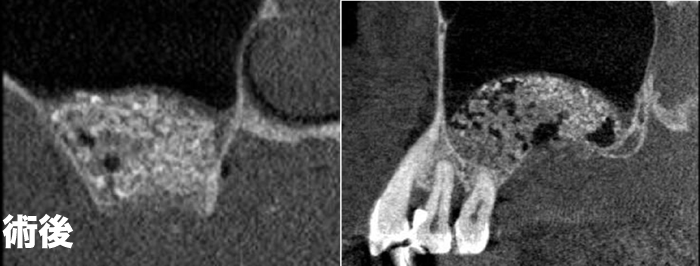

| ケース1 | 術後・術後CTレントゲン写真。 |

| ケース2 | 術後・術後・最終補綴物セット CTレントゲン写真。 |